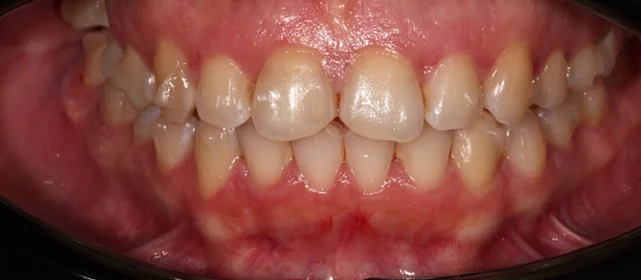

Зубы выровнены, смыкание нормализовано. Установлены несъёмные ретейнеры на обе челюсти, сняты сканы для ретенционных кап. Консультация ортопеда запланирована на более поздний срок.

Решение: Поставили прозрачные элайнеры 3D Smile на обе челюсти. Начали с набора из 34 кап, но в процессе стало понятно, что для полной коррекции нужна доработка — заказали дополнительный набор из 28 кап. Это нормальная ситуация: организм реагирует на перемещение зубов индивидуально, и заранее предсказать точное количество кап до последней штуки невозможно. В итоге 62 капы за 32 месяца — зубы встали на место, смыкание пришло в норму. Параллельно следили за гигиеной, чтобы дёсны оставались здоровыми на протяжении всего лечения.

Основной набор из 34 кап выполнил бо́льшую часть работы, но для финальной коррекции смыкания понадобился дополнительный комплект. Это не редкость — зубы двигаются с разной скоростью, и последние доли миллиметра часто требуют доработки. В итоге получили стабильный результат, который зафиксировали ретейнерами.